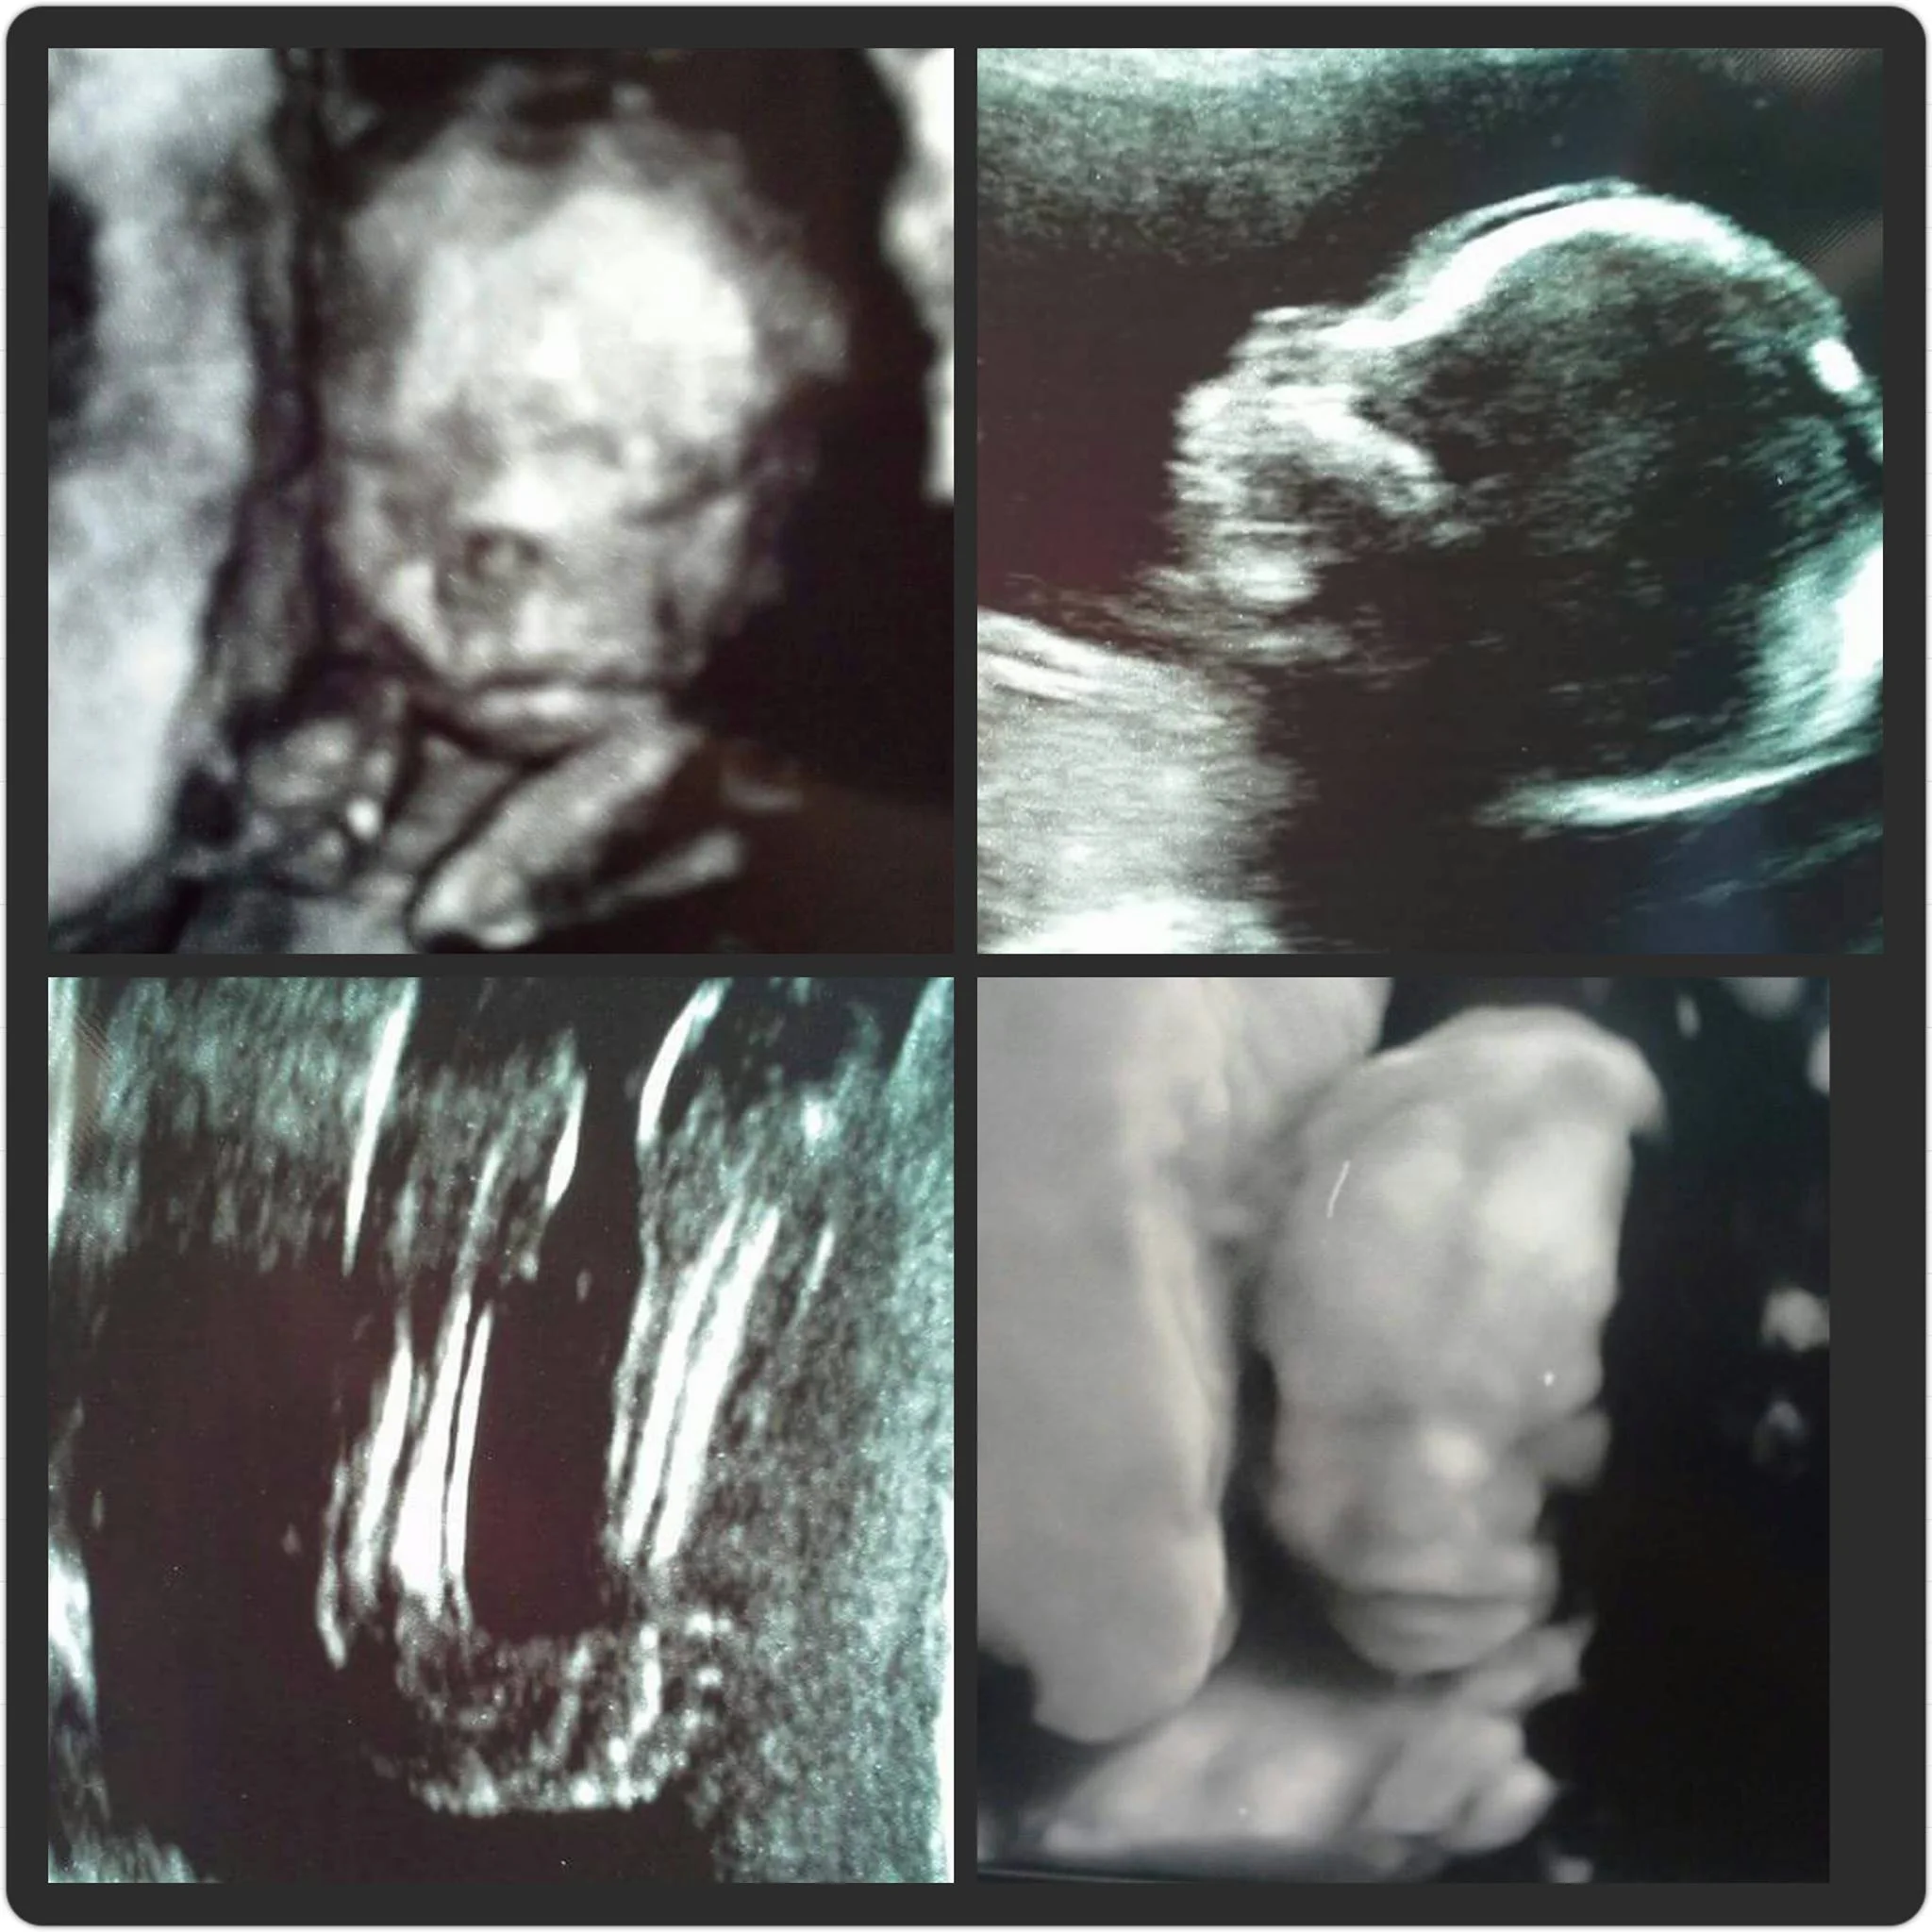

"Early in the summer of 2014 my husband and I announced that we were expecting our third baby, due in January 2015. We were planning our first home birth and we were going to be "team green" and wait until the birth to find out if the baby was a boy or a girl. During my first trimester I couldn't help but feel like something was different about this pregnancy. As I began the second trimester I grew concerned about not feeling any movement from the baby. I started to worry that something could be wrong. I began to ask "what if all of my friends who are due around the same time are bringing home babies and I'm not? What if my baby isn't okay?" Many friends assured me that they had also experienced pregnancies feeling very little movement from baby during the second trimester and everything had turned out fine. I was overthinking it and worrying too much. I tried to relax but I couldn't shake that nagging feeling. When we had our anatomy scan at 19 weeks there was confirmation that my worries weren't for nothing. The baby was not moving, and as the ultrasound technician poked at my belly to try to wake the baby nothing happened. The baby didn't move at all. The limbs were contracted against the body, and the foot that we could see was clubbed. The heart was beating strong, though. There were a few concerns, but the midwife I spoke with said that it could just be a lazy day for the baby. We were set up with an appointment to go to All Children's for a level 2 ultrasound. I had been there before during my second pregnancy when we had to go for a concern about spina bifida, but my son was fine and everything turned out well, so I hoped that it would turn out fine this time, too.

This time, though, it wasn't. We were told that our baby had contracted limbs (arthrogryposis) and clubbed feet, and there was fluid in the feet. One strong possibility was Trisomy 18. We decided to have the Panorama blood test to see what the chances were of it being a chromosomal abnormality. I was given the option of having an amniocentesis but declined because the risks involved felt like too much. The doctor told us that if our baby survived, he or she would most likely be wheelchair bound with little to no ability to control the bladder or bowels. I was asked if I would terminate under any circumstance and I said no. So we did the blood draw, made an appointment for a heart echo ultrasound, and would check on her again a few weeks later. I left with very few answers, a piece of paper with everything we had learned during the ultrasound written on it, and a whole lot of uncertainty. The heart echo ultrasound revealed that the baby's heart was perfect, and it gave me hope. I asked if the technician could try to see if the baby was a boy or a girl. With everything that was happening I just wanted something positive, I wanted to know who my baby was. It was hard to tell because of the position of the legs, but it appeared to be a little girl! I left the appointment feeling like there was hope after all. If the baby's heart was perfect she could survive this, right? We received the results of the panorama test that day, too, and it detected no chromosomal abnormalities and they were also able to tell me that the baby was definitely a girl! We were so hopeful, and we named her Jane Elizabeth. Jane was Cory's grandmother who had passed away before I met him and it happened to be her birthday that day, so Jane was a perfect fit. Elizabeth is my best friend's first name, so that was her middle name. I pulled out the box of clothes I had saved from my first daughter and and finally felt a little bit excited imagining this new baby wearing them. We went to the next ultrasound expecting no changes, we thought it was probably just the arthrogryposis and that we would be able to get treatment for it once she was born, but there was more bad news this time. The doctor said it would be best for my mom and the kids to wait in the waiting room and then she told us that the baby had developed full body hydrops fetalis. I was told that I could either wait it out or have a cesarean section that day. She said that if I chose the c-section they would try to drain the fluid from the baby's body and intubate her and try to save her but her chance of survival was basically zero. I would also have a vertical incision and was told that I would never birth naturally again.